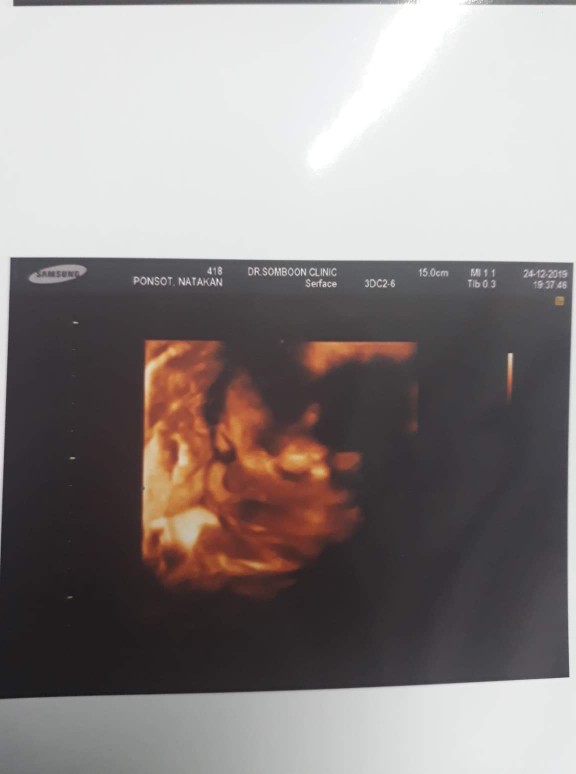

ชัดมากเลยค่ะ

จมูกโด่งค่ะ

ดั้งโด่งจัง